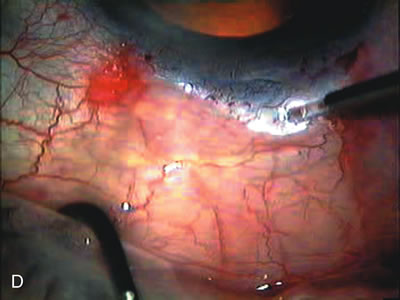

CATARACT EXTRACTION ALONE REDUCES IOP IN MOST EYES WITH ANGLE-CLOSURE GLAUCOMA

Uncomplicated cataract extraction substantially reduces IOP, along with the number of postoperative glaucoma medications in eyes with angle-closure glaucoma.146,147 When preoperative gonioscopy reveals PAS, along with adjacent areas of appositional closure, lens extraction alone in select cases may be a reasonable alternative to filtration surgery.148,149 Phacomorphic angle-closure disease due to enlargement of the lens with progressive angle crowding is eliminated following lens extraction. The width and depth of the anterior chamber angle in eyes with angle-closure glaucoma increases significantly after cataract extraction with IOL implantation and becomes similar to open-angle glaucoma and normal eyes.150,151 (Fig. 5). Combining phacoemulsification, IOL implantation, and limited goniosynechialysis is effective in the treatment of cataract and chronic angle-closure glaucoma.152 Phacoemulsification with implantation of a foldable IOL is more effective in reducing IOP and improving visual acuity than surgical peripheral iridectomy in eyes with acute angle-closure glaucoma.153

Fig. 5. Anterior chamber angle changes associated with lens extraction and PCIOL This 65-year-old Vietnamese woman has a long-standing history of chronic angle-closure glaucoma treated with laser peripheral iridectomy. The optic nerve demonstrated mild glaucomatous damage and IOP was moderately controlled on two antiglaucoma medications. The cataract was removed through temporal clear corneal phacoemulsification with foldable acrylic IOL. A. Symptomatic cataract in narrow-angle glaucoma eye with patent iridectomy. B. Intraoperative goniophotograph showing crowding of angle with increasing narrowness due to phacomorphic component. C. Intraoperative photograph showing temporal clear corneal approach with IOL in the capsular bag. D. Intraoperative goniophotograph demonstrating deepening of chamber angle following lens extraction. Proposed theories for IOP reduction following lens extraction with complete wound closure: